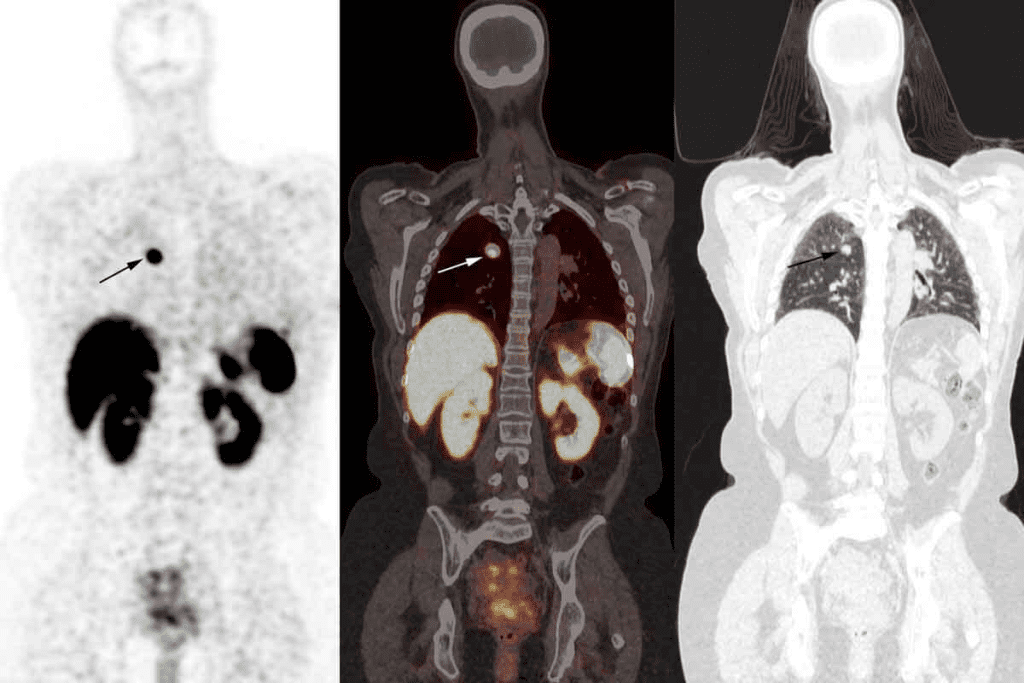

Bone Scans for Cancer Detection

How Bone Scans Identify Cancer Cells

Bone scans find cancer cells by seeing changes in bone activity. Cancer can make bones work more or less, which shows up on scans. “A bone scan is highly sensitive for detecting changes in bone metabolism associated with cancer,” making it a valuable tool in cancer diagnosis.

We inject a radioactive tracer into the patient’s blood. This tracer goes to active bones, which the scan can see. “Hot spots” or “cold spots” on the scan might mean cancer is there.

Primary Bone Cancer vs. Metastatic Bone Disease

Telling primary bone cancer from metastatic bone disease is key for treatment. Primary bone cancer starts in the bone, while metastatic bone disease comes from cancer spreading to the bone. Bone scans help us see how much and where the bone is affected.

Sensitivity and Specificity in Cancer Detection

Bone scans are great at finding bone changes linked to cancer. But, they might not always point to cancer. Other issues, like fractures or infections, can also show up on scans.

To get a clear diagnosis, we use different tests and check-ups. By matching bone scan results with other findings, we can make sure our diagnosis is right. This helps us plan the best treatment.